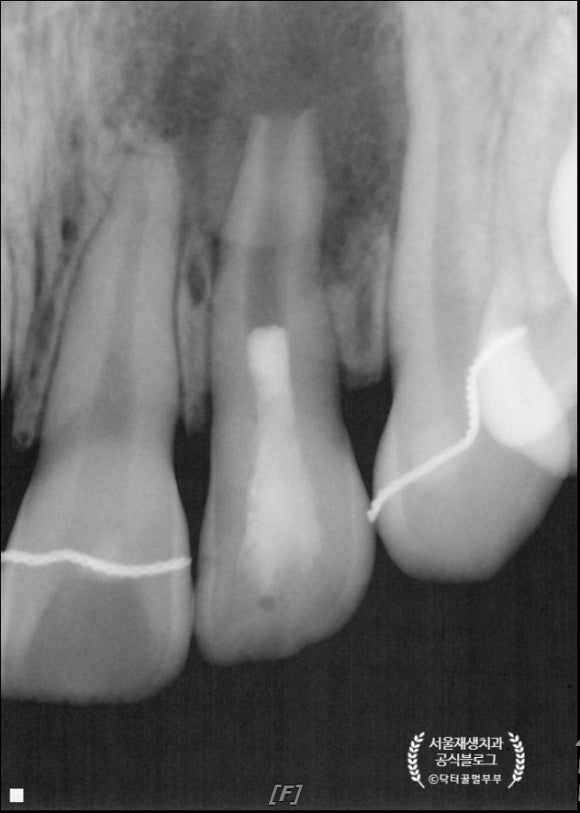

앗, 저런저런......

길다란 바늘이 위치한 치아가 보이시나요?

치아 뿌리를 중심으로 까맣게 뼈가 녹아내린 소견입니다.

성장중이던 치아의 생활력이 상실되어

(=신경이 죽어서)

죽은 조직으로 인해 염증이 유발되고,

치근의 성장 또한 멈춘 전형적인 문제 사례입니다.

원인은 외상이라고 합니다.

예전에 넘어진 적이 있었지만, 당시엔 증상이 없어서 그냥 지나갔다구요.....ㅠ